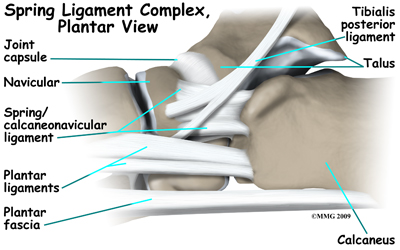

Many small ligaments hold the bones of the foot together. Most of these ligaments form part of the joint capsule around each of the joints of the foot. A joint capsule is a watertight sac that forms around all of the joints of the foot. The capsule is made up of the ligaments around the joint and the soft tissues between the ligaments that fill in the gaps and form the sac.

The plantar fascia is a thick band of ligamentous tissue on the bottom of the foot that extends from the heel to the toes. When you pull your toes back with one hand, you will be able to feel this band with your fingers of the other hand. This fascia is also critical in supporting the long arch of the foot and in creating the rigid foot structure mentioned above.

The spring ligament complex, which supports the talonavicular joint, is often involved in the flatfoot condition. The spring ligament complex works with the posterior tibial tendon and the plantar fascia to support and stabilize the longitudinal arch of the foot. Laxity of the ligaments that support this arch can result in deformity of the foot and/or ankle resulting in pes planus.

Foot Anatomy Ligaments & Tendons